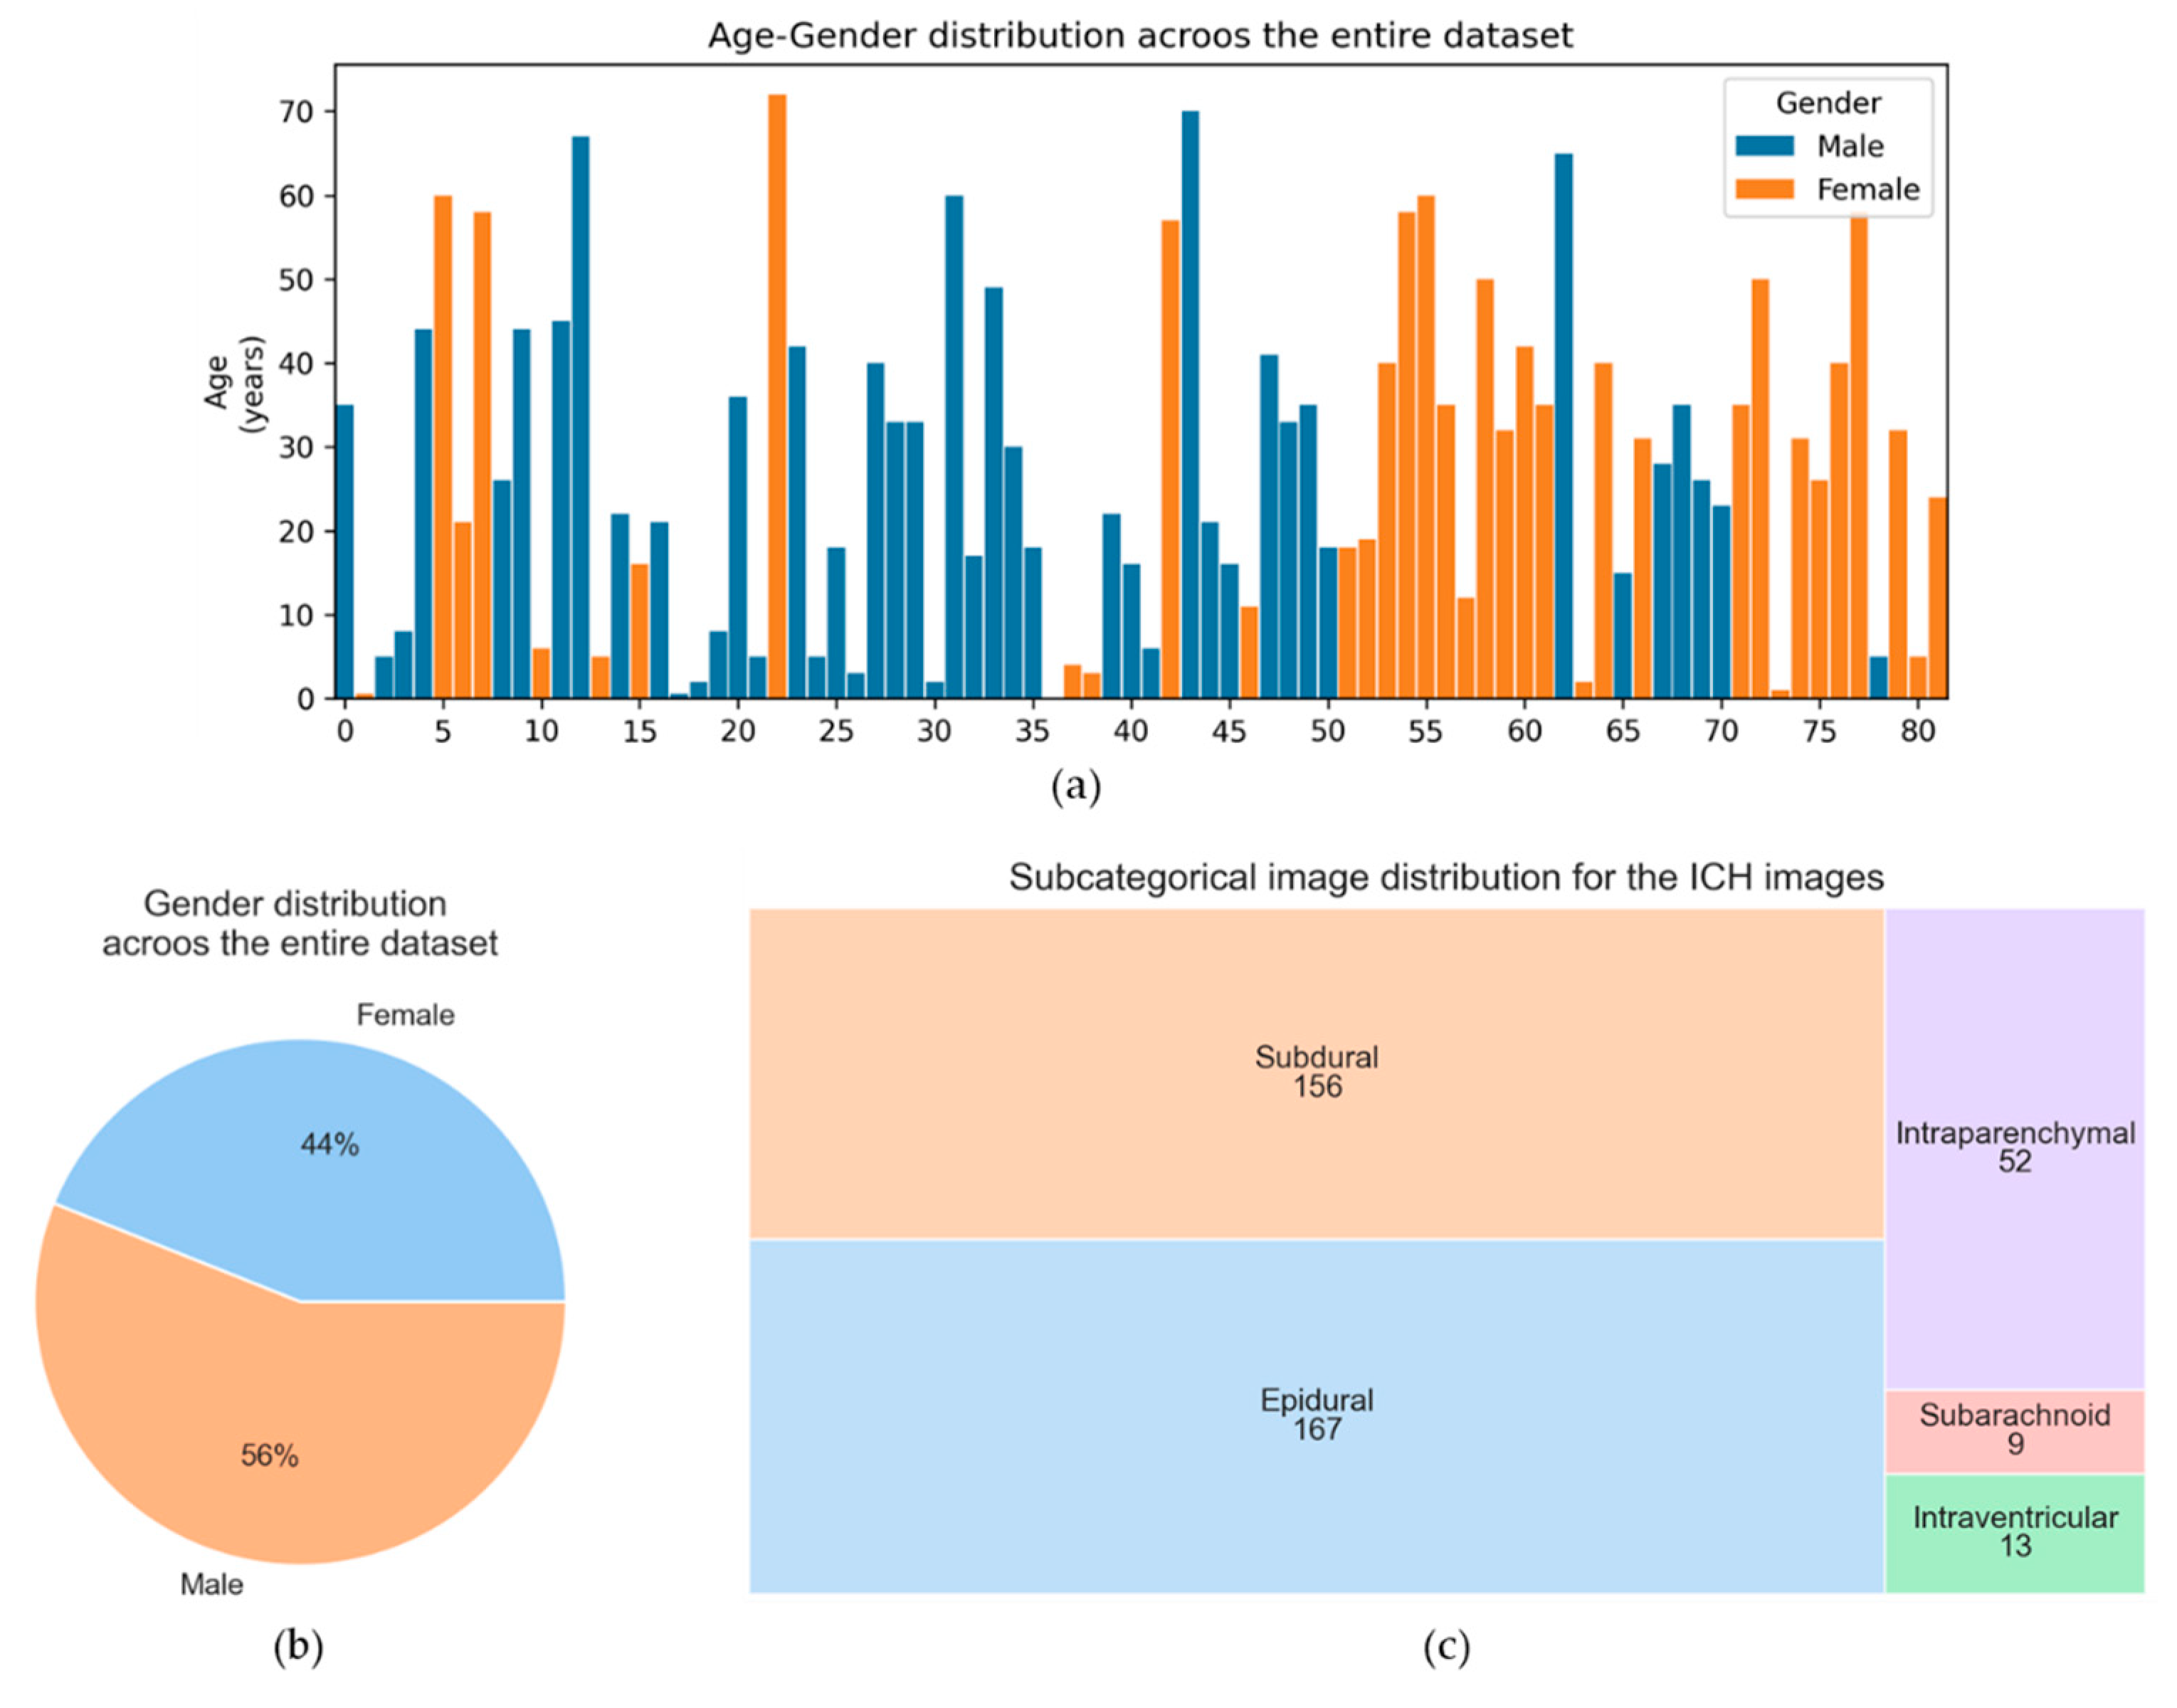

2.1. Dataset Description